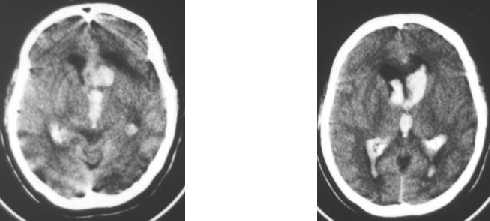

Nontraumatic ICH : intraventricular hemorrhage